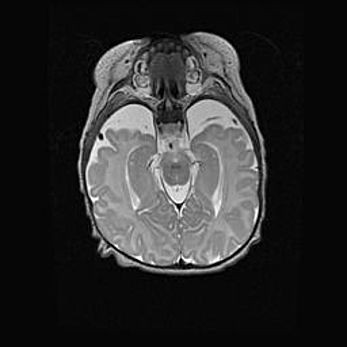

Мальформация Денди-Уокера. Киста задней черепной ямки.

Агенезия мозолистого тела.

Возраст: 2,5 месяца

Вес: 2420 г

Пол: женский

Окружность головы: 37 см

Срок гестации: 32 недели

Мальформация Денди—Уокера — редкий вид патологии ЦНС, представляющий собой врожденный порок развития каудального отдела ствола и червя мозжечка, ведущий к неполному раскрытию срединной (Мажанди) и латеральных (Лушка) апертур IV желудочка мозга. Для этогно синдрома характерна триада симптомов: гипотрофия червя мозжечка и/или полушарий мозжечка, кисты задней черепной ямки, гидроцефалия различной степени. В 70% случаев порок сочетается и с другими аномалиями головного мозга, в частности с агенезией мозолистого тела.